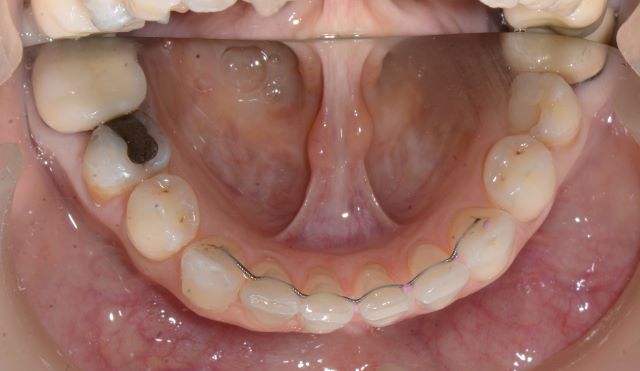

שימוש בכפתורים וגומיות בין לסתיות

לעיתים במהלך הטיפול ישנו צורך בסגירת מנשך פתוח שנובע מעמדה לקויה של הלסתות ו/או השיניים ואינו מאפשר מגע בין השיניים העליונות לשיניים התחתונות, לצורך זה יש לעיתים להרכיב גומיות בין לסתיות שלרוב מעוגנות בכפתורים מהסוג המודגם בתמונות.